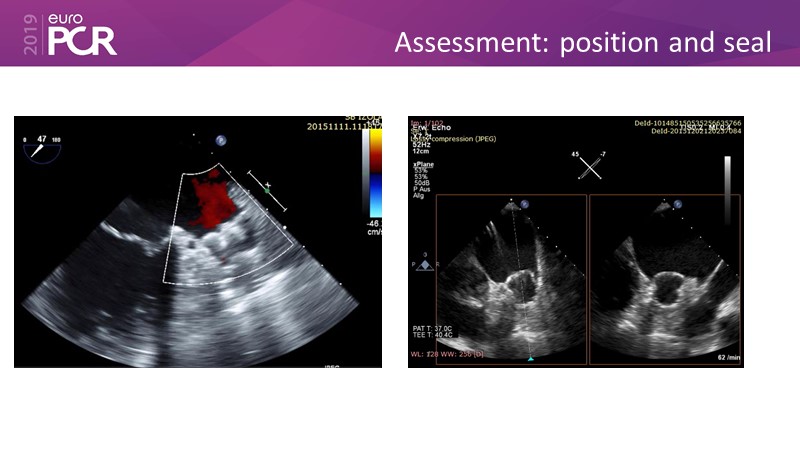

Optimising procedural outcome and safety

Previous Next